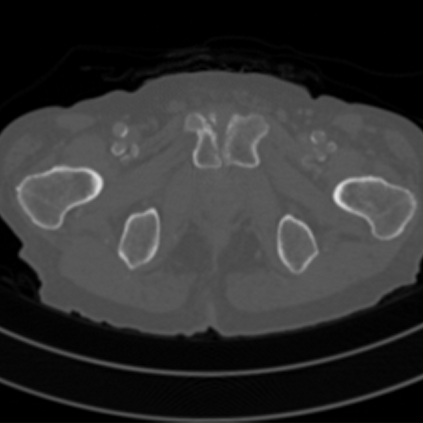

Sparse-view computed tomography (CT) -- using a small number of projections for tomographic reconstruction -- enables much lower radiation dose to patients and accelerated data acquisition. The reconstructed images, however, suffer from strong artifacts, greatly limiting their diagnostic value. Current trends for sparse-view CT turn to the raw data for better information recovery. The resultant dual-domain methods, nonetheless, suffer from secondary artifacts, especially in ultra-sparse view scenarios, and their generalization to other scanners/protocols is greatly limited. A crucial question arises: have the image post-processing methods reached the limit? Our answer is not yet. In this paper, we stick to image post-processing methods due to great flexibility and propose global representation (GloRe) distillation framework for sparse-view CT, termed GloReDi. First, we propose to learn GloRe with Fourier convolution, so each element in GloRe has an image-wide receptive field. Second, unlike methods that only use the full-view images for supervision, we propose to distill GloRe from intermediate-view reconstructed images that are readily available but not explored in previous literature. The success of GloRe distillation is attributed to two key components: representation directional distillation to align the GloRe directions, and band-pass-specific contrastive distillation to gain clinically important details. Extensive experiments demonstrate the superiority of the proposed GloReDi over the state-of-the-art methods, including dual-domain ones. The source code is available at https://github.com/longzilicart/GloReDi.